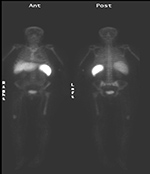

| Figure 32A |

Figure 32B |

| 63 year-old woman with right femoral hardware for 3 years presented with right leg pain. Whole body Tc-99m HMPAO tagged WBC (A) scan demonstrated focal abnormal activity in the distal right femur which may represent infection or focal marrow. Tc99m sulphur colloid bone marrow scan (B) four weeks later demonstrates similar focal uptake in the distal right femur confirming the etiology as uptake in displaced marrow and not infection. |